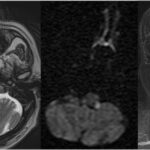

La lesión se localiza en la porción dorsolateral del bulbo raquídeo, generalmente en el territorio irrigado por la arteria cerebelosa posteroinferior, identificable en resonancia magnética como un foco hiperintenso en secuencias T2 y FLAIR, con restricción a la difusión y disminución de la señal en el mapa ADC en la fase aguda. La afectación del pedúnculo cerebeloso inferior y de los núcleos vestibulares, habitualmente en el bulbo lateral rostral, explica el vértigo y la ataxia ipsilateral, mientras que el compromiso del núcleo y tracto espinal del nervio trigémino, de disposición posterolateral, se traduce en pérdida de la sensibilidad termoalgésica facial ipsilateral. En lesiones con mayor extensión medial o caudal, puede observarse compromiso del núcleo ambiguo, con disfagia y disfonía(3) y cuando se afectan las fibras simpáticas descendentes se asocia la aparición de síndrome de Horner ipsilateral. La afectación combinada de estas estructuras explica el patrón sindrómico característico del síndrome de Wallenberg, diferenciándolo de otros infartos medulares con compromiso medial o ventral. Asimismo, se ha descrito que los pacientes con infartos bulbares laterales presentan alteraciones faríngeas más severas que aquellos con infartos hemisféricos, subrayando la importancia de la localización anatómica precisa en la interpretación imagenológica del cuadro clínico.(4) En el momento del inicio, hasta un 50-70% de los pacientes presentan síntomas vestibulares y alteraciones sensitivas cruzadas,(2) hallazgos coherentes con la topografía observada en la resonancia magnética.